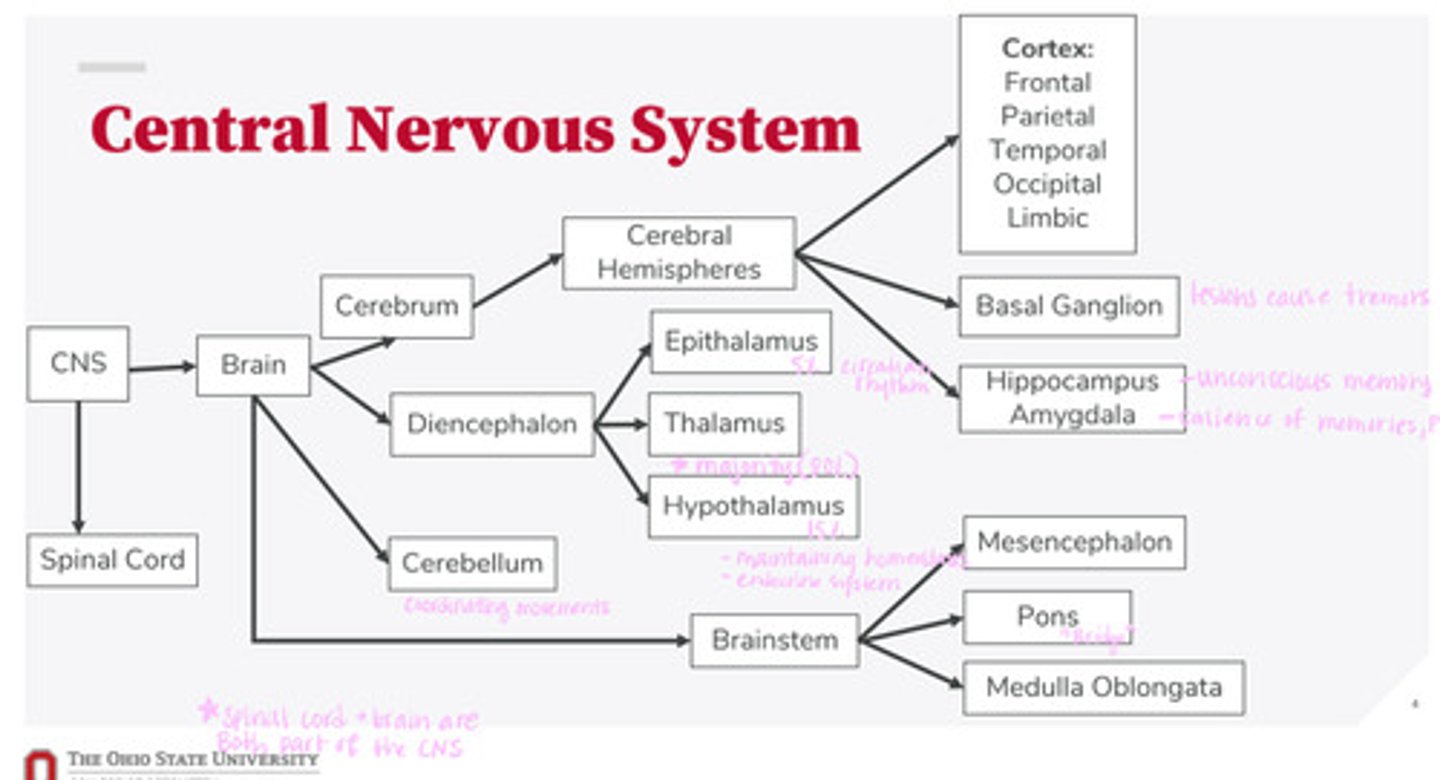

-brain

-spinal cord

What are the 2 divisions of the CNS?

-cerebrum

-diencephalon

-cerebellum

-brainstem

What are the 4 divisions of the brain?

-epithalamus

-thalamus

-hypothalamus

What are the 3 divisions of the diencephalon?

-mesencephalon

-pons

-medulla oblongata

What are the 3 divisions of the brainstem?

-cortex

-basal ganglion

-hippocampus

-amygdala

What are the divisions of the cerebral hemispheres?

-frontal lobe

-parietal lobe

-temporal lobe

-occipital lobe

-limbic system

What are the divisions of the cortex?

coordinating movements

What is the function of the cerebellum?

thalamus

A majority of signals from the diencephalon flow into where?

circadian rhythm

What is the function of the epithalamus?

-maintaining homeostasis

-endocrine system function

What is the function of the hypothalamus?

tremors

Lesions on the basal ganglion cause what?

hippocampus

What part of the brain is in control of unconscious memory?

amygdala

What part of the brain is in control of the salience of memories (PTSD)?

The bridge between the mesencephalon and the medulla oblongata

What is the function of the pons?